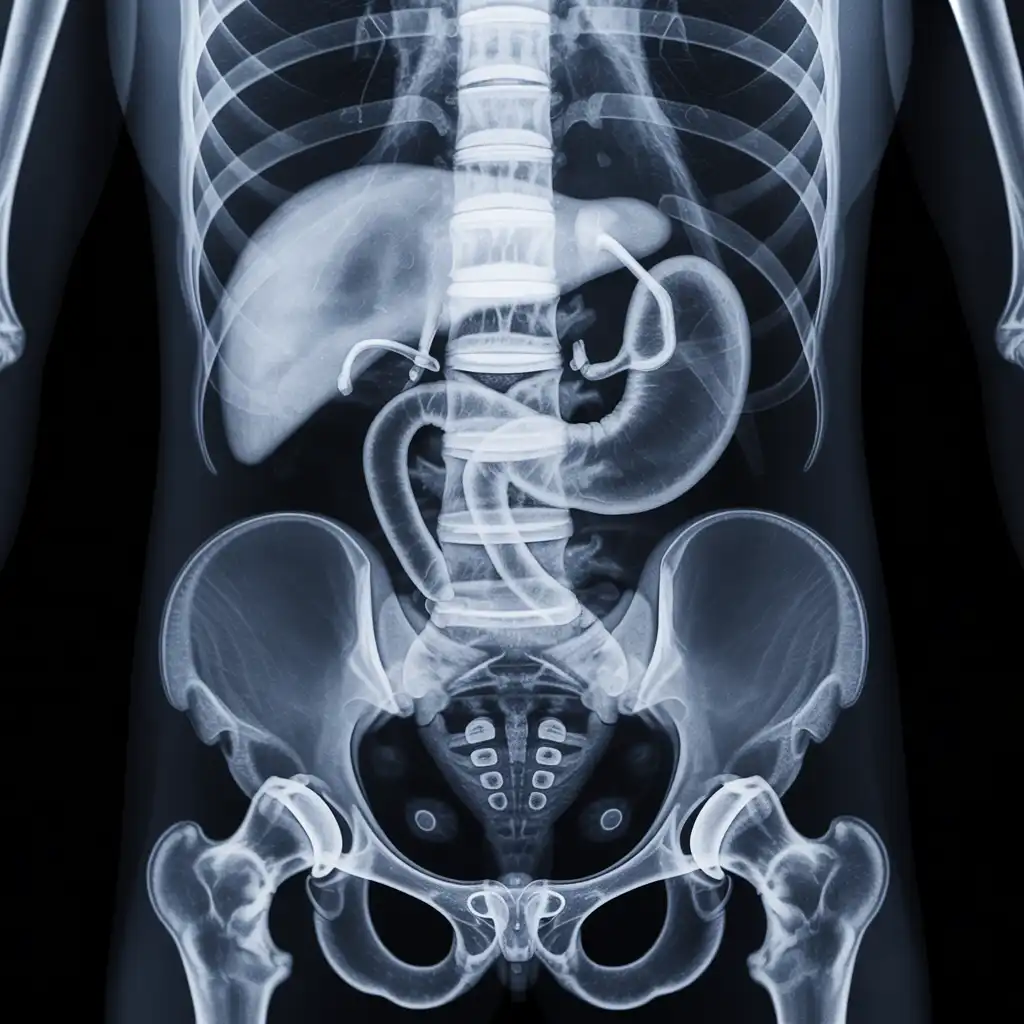

Il professionista entra con apparecchiature a basso dosaggio e schermi protettivi: bastano 2 × 2 m di spazio vicino al letto o alla poltrona. In pochi minuti acquisisce immagini HD, proprio come in un reparto ospedaliero.

Le immagini (formato DICOM) vengono caricate su un server crittografato e inviate immediatamente al radiologo. Se servono scatti aggiuntivi, il tecnico resta in collegamento video per eseguirli al volo.

Il medico radiologo analizza le immagini e firma il referto digitale all’istante. Ricevi il referto cartaceo e le immagini su chiavetta USB consegnati direttamente a casa tua subito dopo l'esame.

Usiamo le stesse apparecchiature certificate CE dei reparti ospedalieri, calibrate regolarmente. I referti sono validi per visite specialistiche, pronto soccorso e pratiche assicurative, e restano archiviati per 10 anni per ogni esigenza futura.